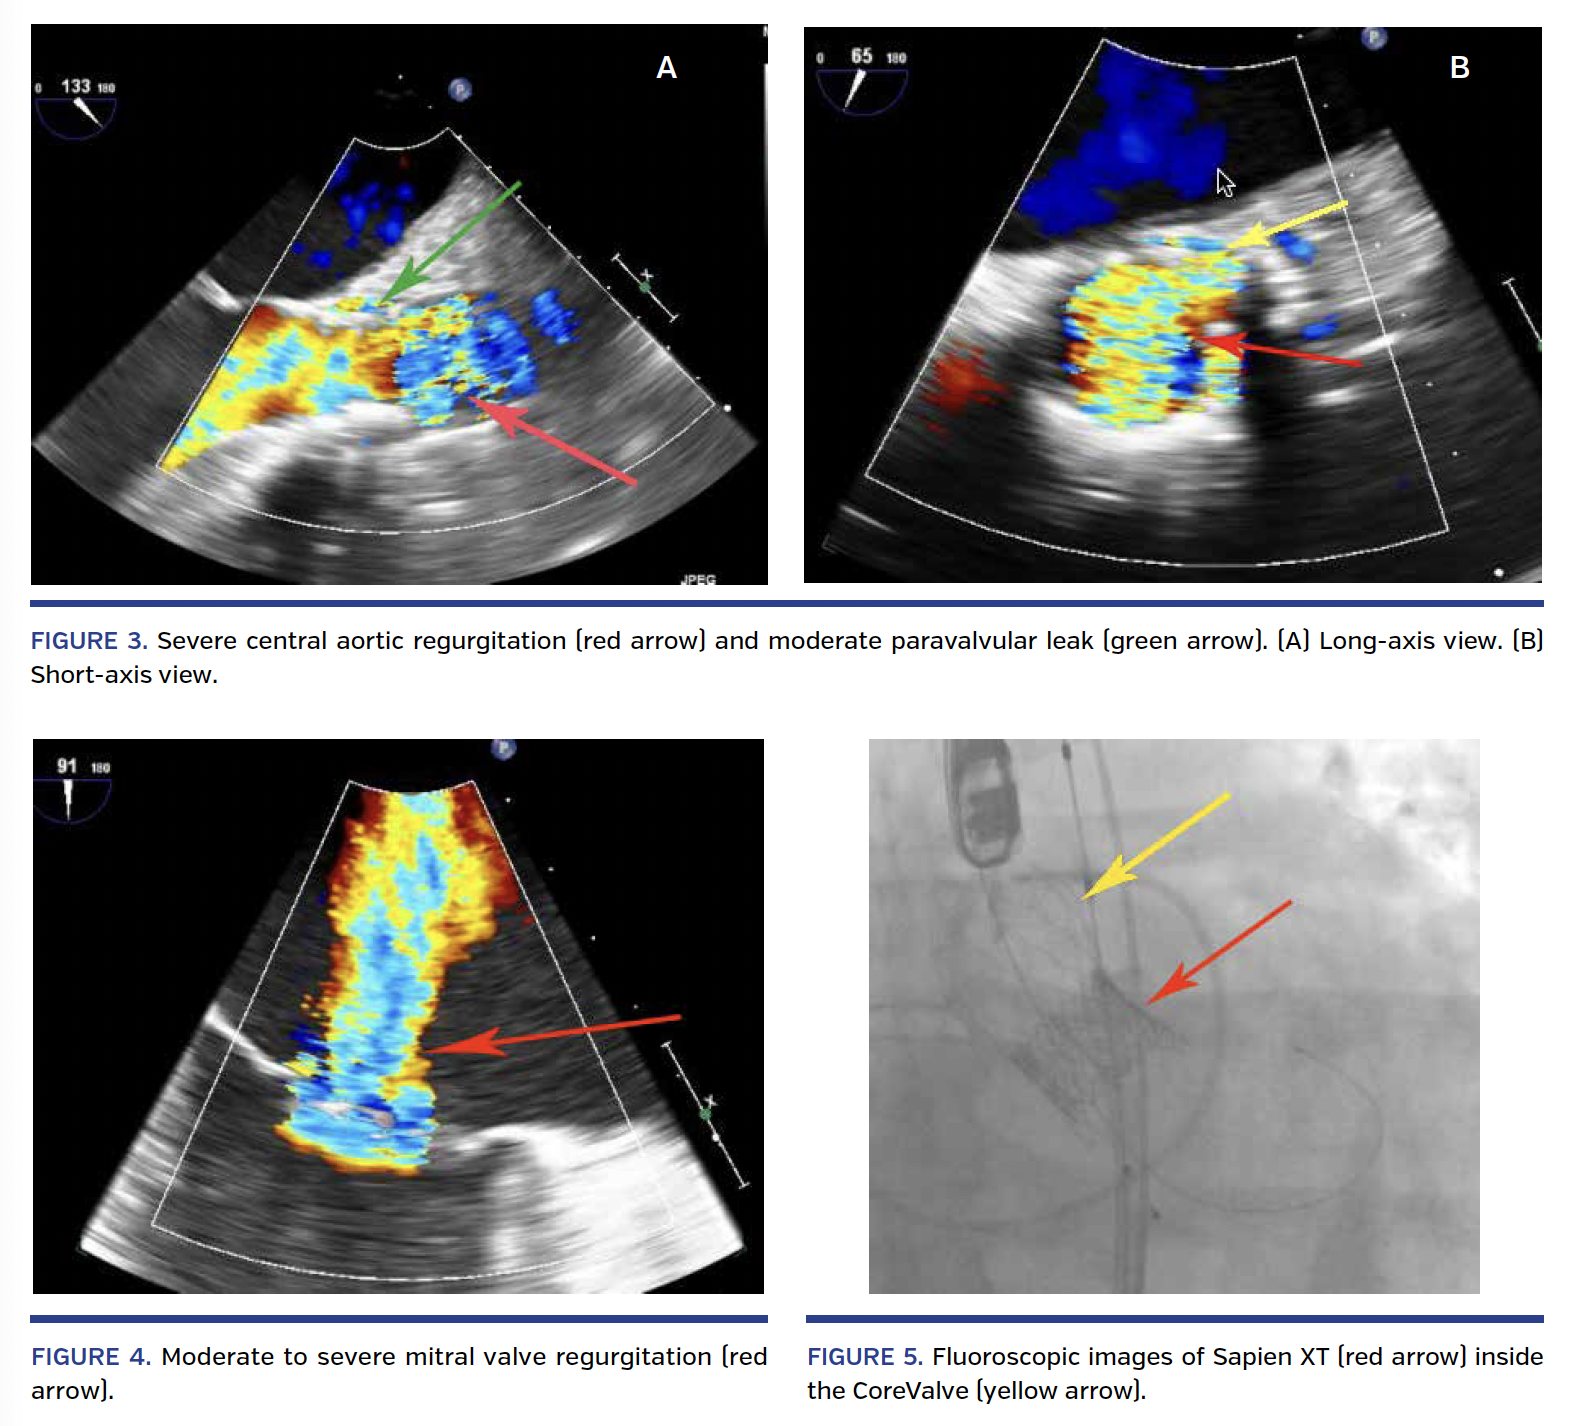

significant pulse pressure present. It was felt that due to the presence of a large annulus, placing another CoreValve with a VinV configuration would not reduce the PVL. The procedure was concluded with a plan to clinically reevaluate the patient over the next several months. The patient was discharged home on day 4 post operation. Over the next 2 months, the patient’s functional capacity slowly declined. On his follow-up visits, the patient stated that he never had any relief of his symptoms following his TAVR procedure. He was admitted 1 week prior to his second TAVR procedure with acute decompensated heart failure for which he was treated medically. His repeat TEE showed severe central aortic valve regurgitation and a moderate PVL with pressure half time (Figure 3). The patient also had moderate mitral valve regurgitation (Figure 4).

His case was again discussed at our heart team meeting. It was decided to perform a repeat TAVR procedure using a VinV approach with a 29 mm Sapien XT valve. The goal of this second TAVR procedure was to eliminate the central aortic valve regurgitation and reduce the PVL.